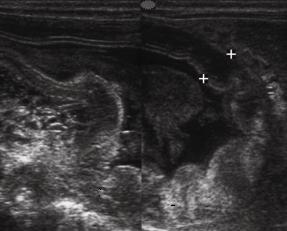

Image echographique de

l' estoma en coupe axiale incline .Epaiseur de

la musculeuse de la paroi est marquee de 4mm a 5mm

en estoma distendu |

Antre

gastrique : epaisseur de la pảroi de antre gastrique

varie entre 3-4mm au niveau de la region pylorique |